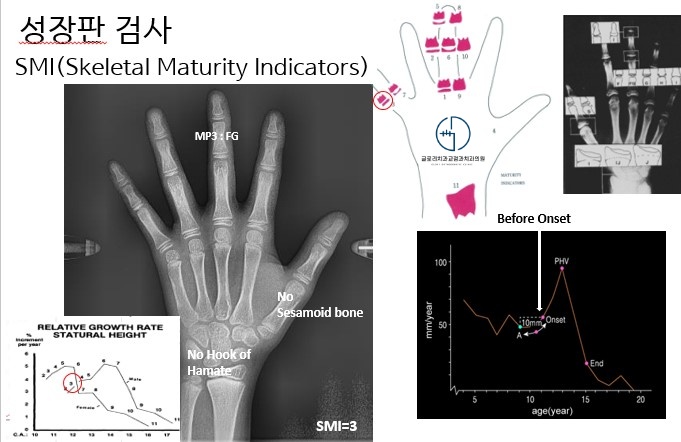

이중에서도 성장기 어린이는 수완부 방사선 촬영으로 현재 뼈의 성장 단계와 남아있는

성장량을 확인하는 과정이 중요합니다.

중랑구 교정치과 에서 설명드리는 수완부 방사선이란 손목과 손가락 뼈의 발달

상태를 확인하여 환자가 성장의 어느 단계에 있는 지 파악하는 검사를 말합니다.

이를 통해 시기를 고려한 교정의 적절한 시작 시점과 치료 방향을 정확하게 설정할 수 있는 것입니다.

현재 수완부 사진을 기준으로 평가한 발달 단계에서 11단계 중 3단계에 해당하는 상태로 확인됩니다.

이는 본격적인 성장 피크가 시작되기 직전 단계로 턱뼈와 치열의 성장이

앞으로 활발하게 이루어질 가능성이 높은 시기입니다.

즉 이러한 시기에 치열을 배열하는 것 뿐 아니라 교정을 통해

턱의 관계까지 유리하게 유도할 수 있는 시점이라 볼 수 있습니다.